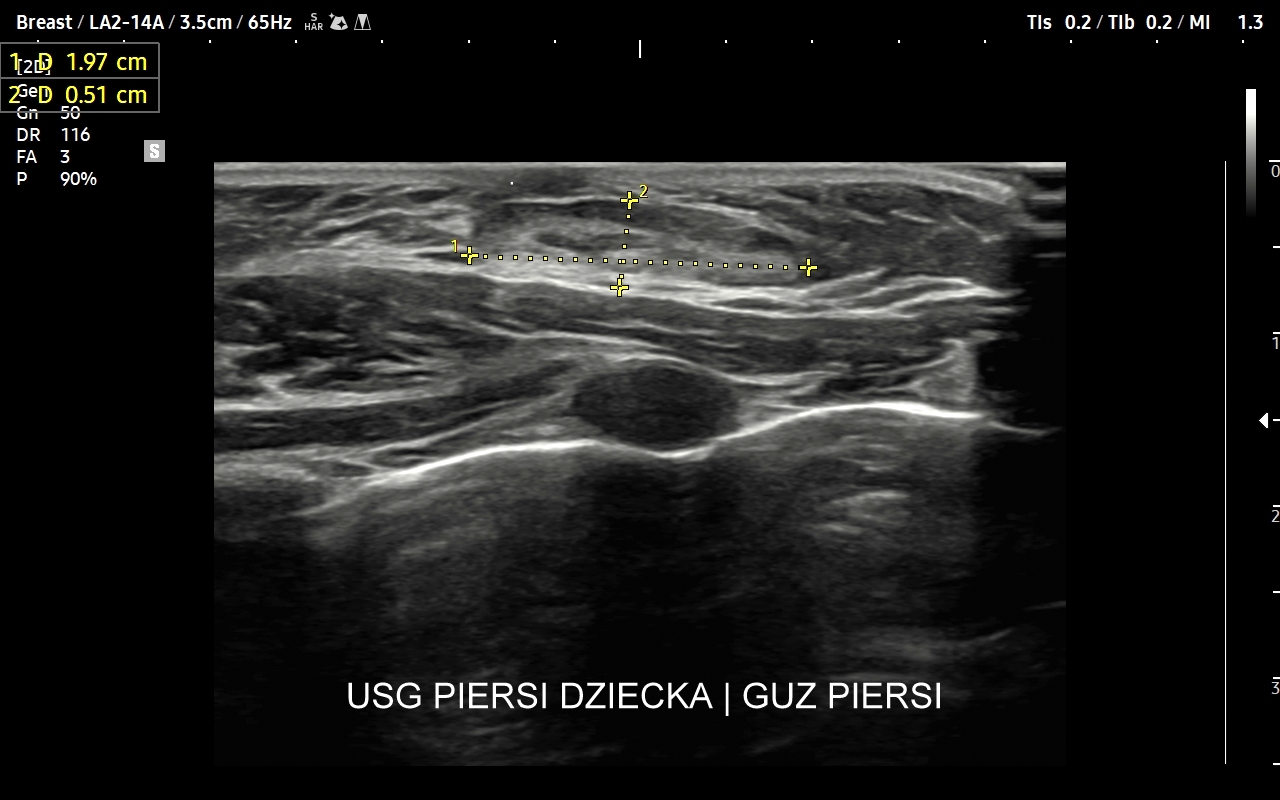

USG piersi u dzieci

Najczęstszym wskazaniem do badania gruczołu piersiowego u dziewczynek jest stwierdzenie przedwczesnego dojrzewania płciowego (ang. precoxious puberty), inaczej pokwitania,  w tym przedwczesnego rozwoju gruczołów piersiowych (łac. thelarche praecox), które jest najczęstszą formą przedwczesnego pokwitania. Badanie USG jest w takiej sytuacji częścią diagnostycznego postępowania endokrynologicznego. W rzadszych przypadkach powiększenia gruczołów piersiowych u dzieci znajdowane są guzy lite, np. tłuszczako-włókniaki.